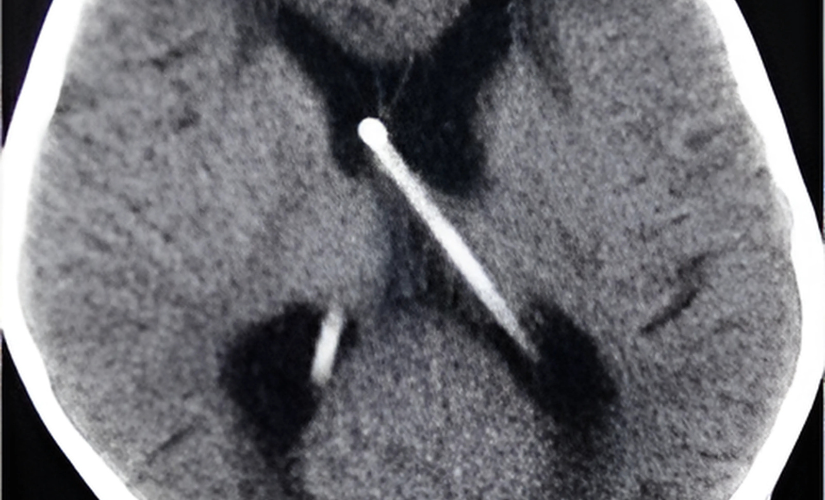

• Intrathecal Baclofen Pump (ITB): A small device implanted under the skin delivers continuous doses of muscle relaxant directly into the spinal fluid, providing sustained relief.